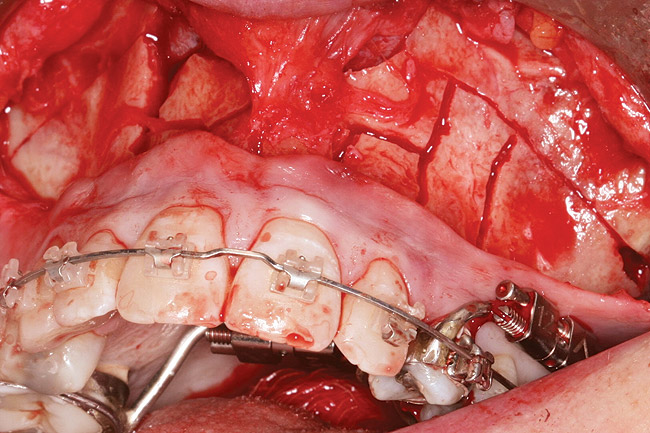

Fig 4. Note gingival inflammation caused by biologic width violation. Provisional restorations were placed on Nos. 6, 8, 9, and 11, and corticotomies were performed from Nos. 3 to 14.

Figure 4